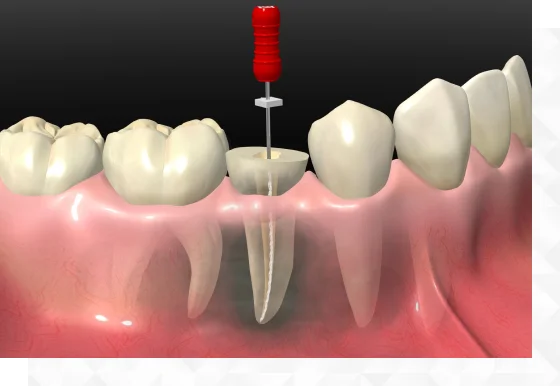

根管治療について

根管治療で歯を残す選択ができます

歯の根の治療のことを根管治療と呼びます。むし歯が進行した場合に行われることがあり、神経を含む歯髄や歯根の感染部分を取り除く処置がされます。根管治療のメリットは腫れや痛みを改善させるだけでなく、歯を抜かずに済むことがあげられます。ご自身の歯を守るためにも、異変があればお早めの受診を推奨いたします。